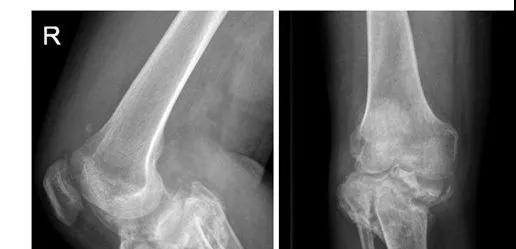

膝关节术前x光片

陈先生抱着一丝希望找到了骨科主任关振鹏教授并入住病房。入院检查显示陈先生有严重的下肢畸形,膝关节肿大、积液,双下肢乏力,膝周痛觉缺失,关节活动障碍,情况非常复杂。影像学提示膝关节对位不良,关节半脱位,关节间隙不规则,胫骨上段干骺端结构紊乱、胫骨平台大面积塌陷,呈现陈旧性粉碎骨折表现,局部骨缺损严重。在仔细分析陈先生的病情后,关主任鼓励陈先生要重燃战胜疾病的信心,准备为他实施人工膝关节置换手术,帮助他重新站起来!